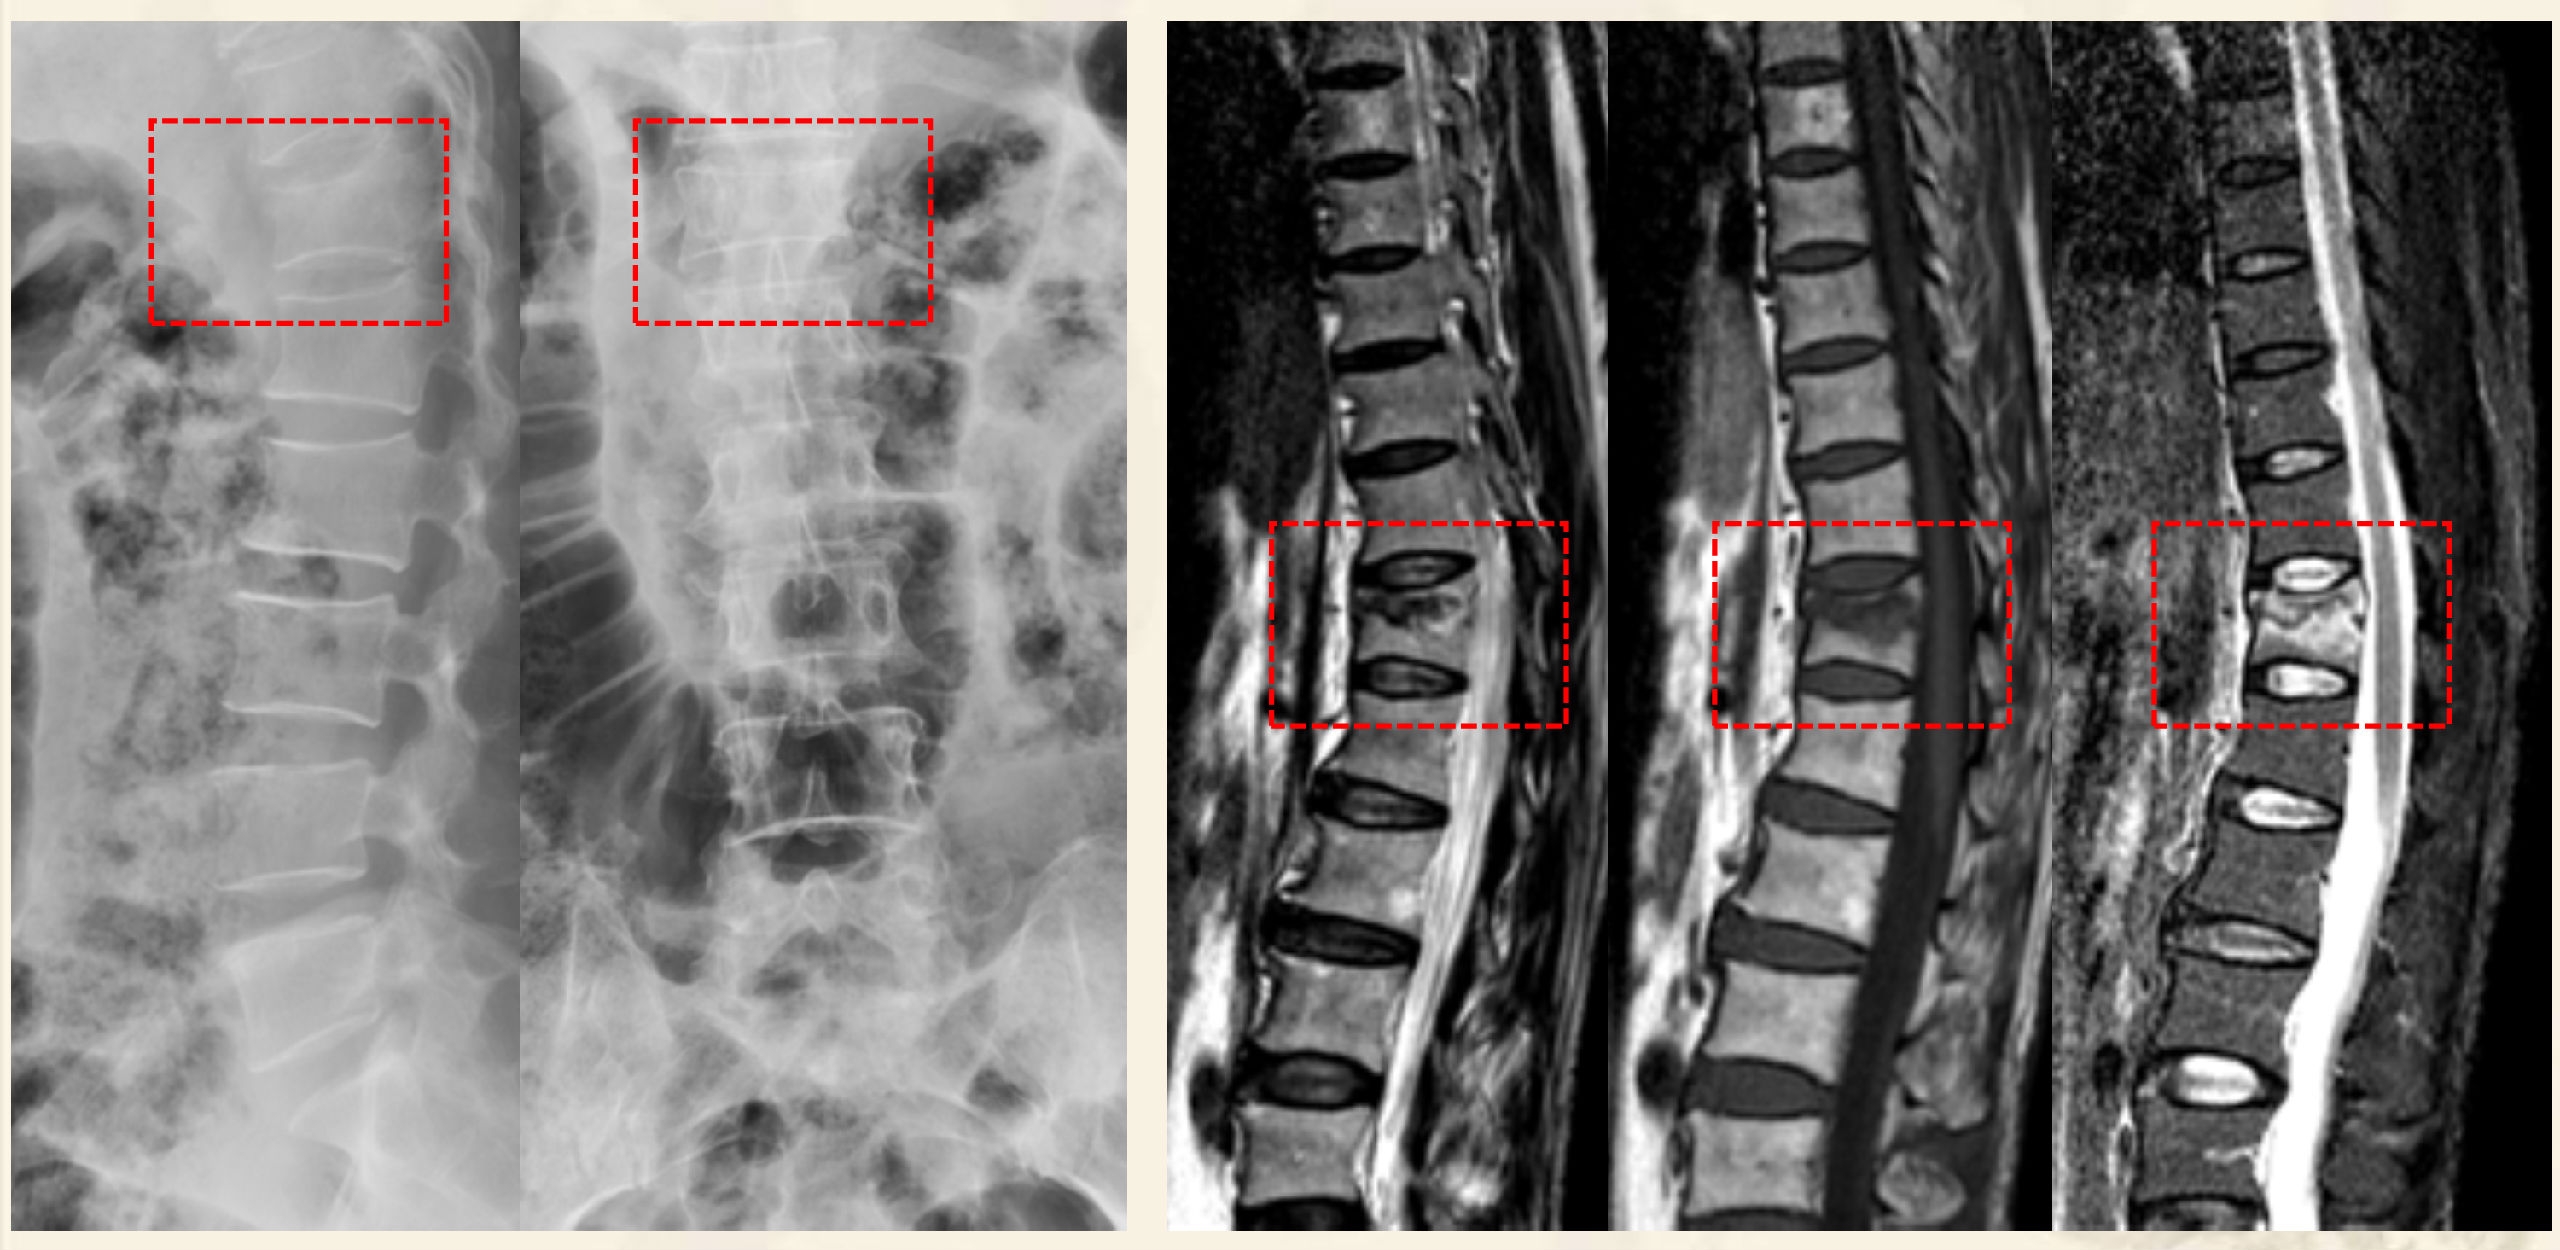

两大类型:①压缩后嵌插型,②压缩后自动复位裂隙型

压缩后嵌插型

压缩后自动复位裂隙型

压缩后嵌插型骨折线,CT:高密度带、MRI低信号带。

压缩后自动复位裂隙型,CT:裂隙,MRI:低信号区(气体)

CT:裂隙,MRI:高信号区(液体)

术前X线

术前MRI